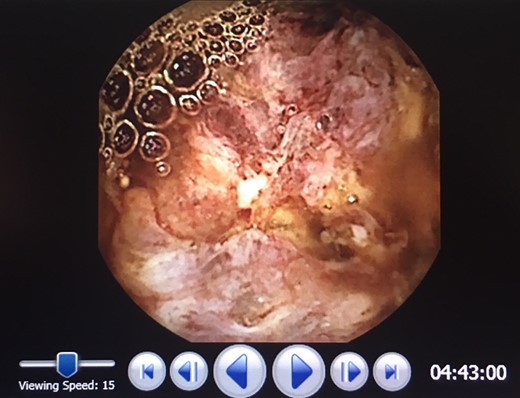

In 2017, repeat imaging showed resolution of all liver metastases, and the patient’s PSA was <0.1. While he had responded excellently to treatment, the patient had developed parastomal hernias around both the colostomy and ileal conduit. Between 2015 and 2017, the patient presented to hospital twice with features suggestive of small bowel obstruction. At the time, this was believed to be related to the hernias and therefore, the patient was planned for surgical repair of these hernias. During pre-operative workup, investigations revealed the patient to be anaemic with a haemoglobin of 80 and a ferritin of 11. Gastroscopy and colonoscopy revealed no abnormality; however, a pill cam demonstrated a single large lesion in the jejunum (Fig. 1). An MRI enterography was arranged to further characterize the lesion (Fig. 2). Given the excellent response to treatment, resolution of all liver metastasis and undetectable PSA levels a prostate cancer metastasis was not suspected. As the nature of this lesion was uncertain, a decision was made to perform a diagnostic laparotomy at time of hernia repair with small bowel resection if indicated.